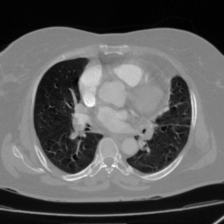

Table 2 presents a quantitative comparison between the proposed DAUNet and several representative state-of-the-art segmentation models, including CNN-based, transformer-based, and hybrid architectures. The comparison is conducted on the FUMPE dataset using Dice Similarity Coefficient (DSC) and 95th percentile Hausdorff Distance (HD95), together with model parameter count as a measure of computational efficiency.

As shown in Table 2, the proposed DAUNet achieves the best overall segmentation performance, attaining a Dice score of 88.80% and the lowest boundary error with an HD95 of 2.57. These results indicate superior overlap accuracy and more precise boundary delineation compared to all competing methods. In addition, DAUNet maintains a significantly lower model complexity, requiring only 21.07M parameters, which is substantially fewer than several strong baselines.

Notably, models with considerably higher parameter counts, such as SCUNet++ (60.11M), do not achieve comparable segmentation accuracy or boundary robustness on this dataset. Transformer-based and hybrid models, including TransAttUNet and FAT-Net, demonstrate improved performance over classical UNet variants; however, they remain inferior to DAUNet in both DSC and HD95, while requiring higher computational cost.

Overall, these results highlight the effectiveness of the proposed lightweight architecture for pulmonary embolism segmentation. DAUNet consistently delivers superior accuracy and robustness while maintaining a compact model size, making it well suited for deployment in real-time and resource-constrained clinical environments.